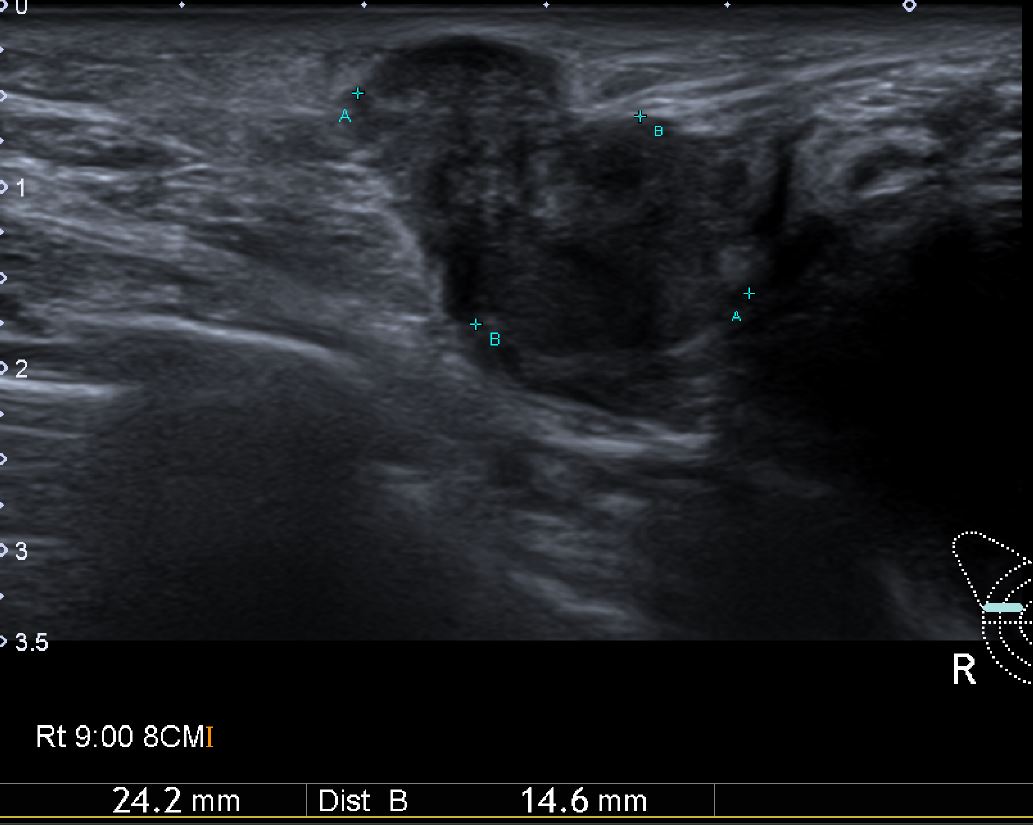

2달전부터 우측유방에 만져지는 혹있어 내원하신 40대 여자환자분으로

본원에서 우측유방 9시 방향에 조직검사 시행후 침윤성 유방암 진단되셨습니다.